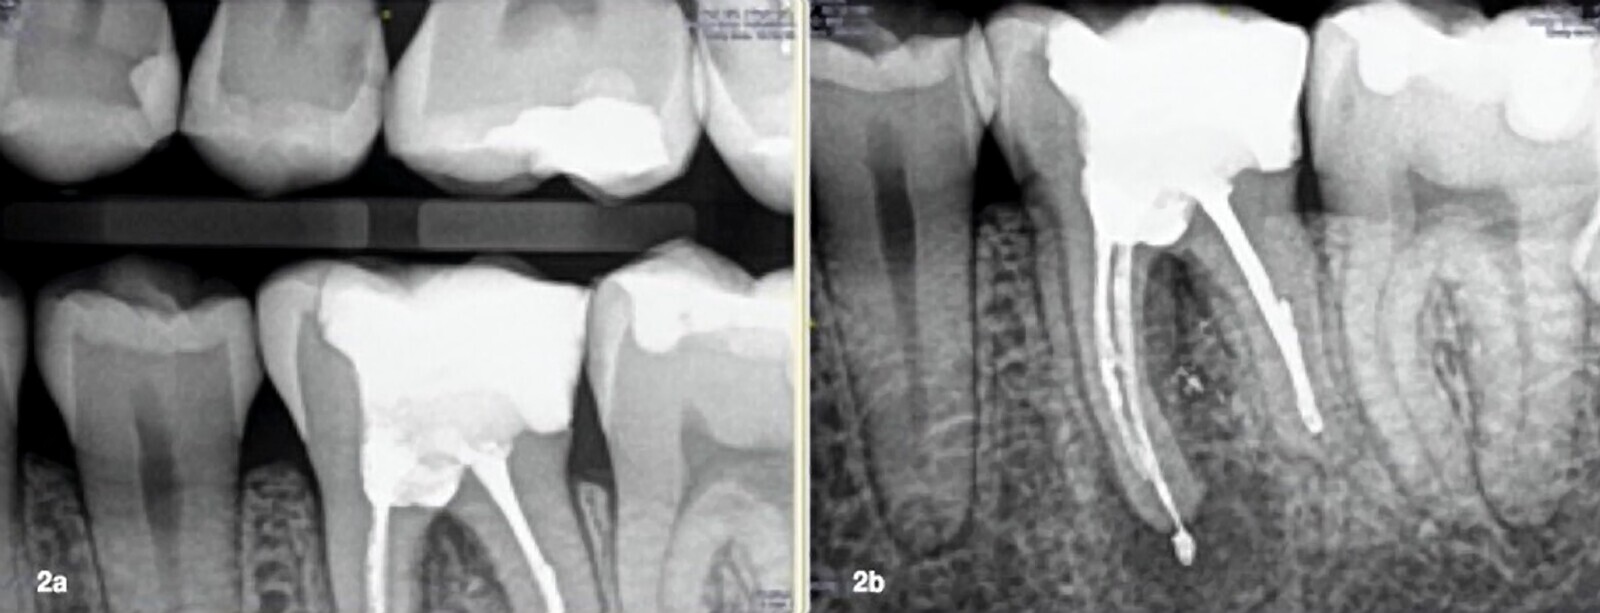

Figs. 2a y 2b. Radiografías de aleta de mordida y periapical inicial.